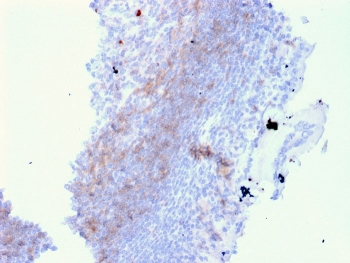

IHC staining of FFPE human lymph node with CD72 antibody (clone BU40). HIER: boil tissue sections in pH9 10mM Tris with 1mM EDTA for 20 min and allow to cool before testing.

IHC staining of FFPE human lymph node with CD72 antibody (clone BU40). HIER: boil tissue sections in pH9 10mM Tris with 1mM EDTA for 20 min and allow to cool before testing.